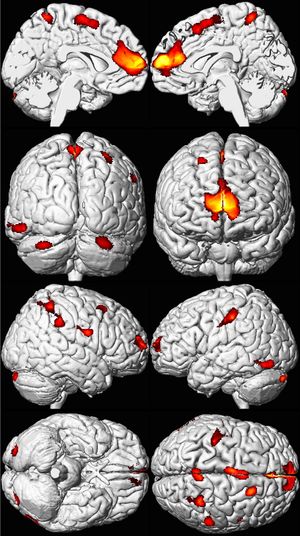

Eight MRI views of a brain in black and white, with yellow, orange, and red areas overlaid in spots mainly toward the front.

The brains of adults who were exposed to lead as children show decreased volume, especially in the prefrontal cortex, on MRI. Areas of volume loss are shown in color over a template of a normal brain.[56]